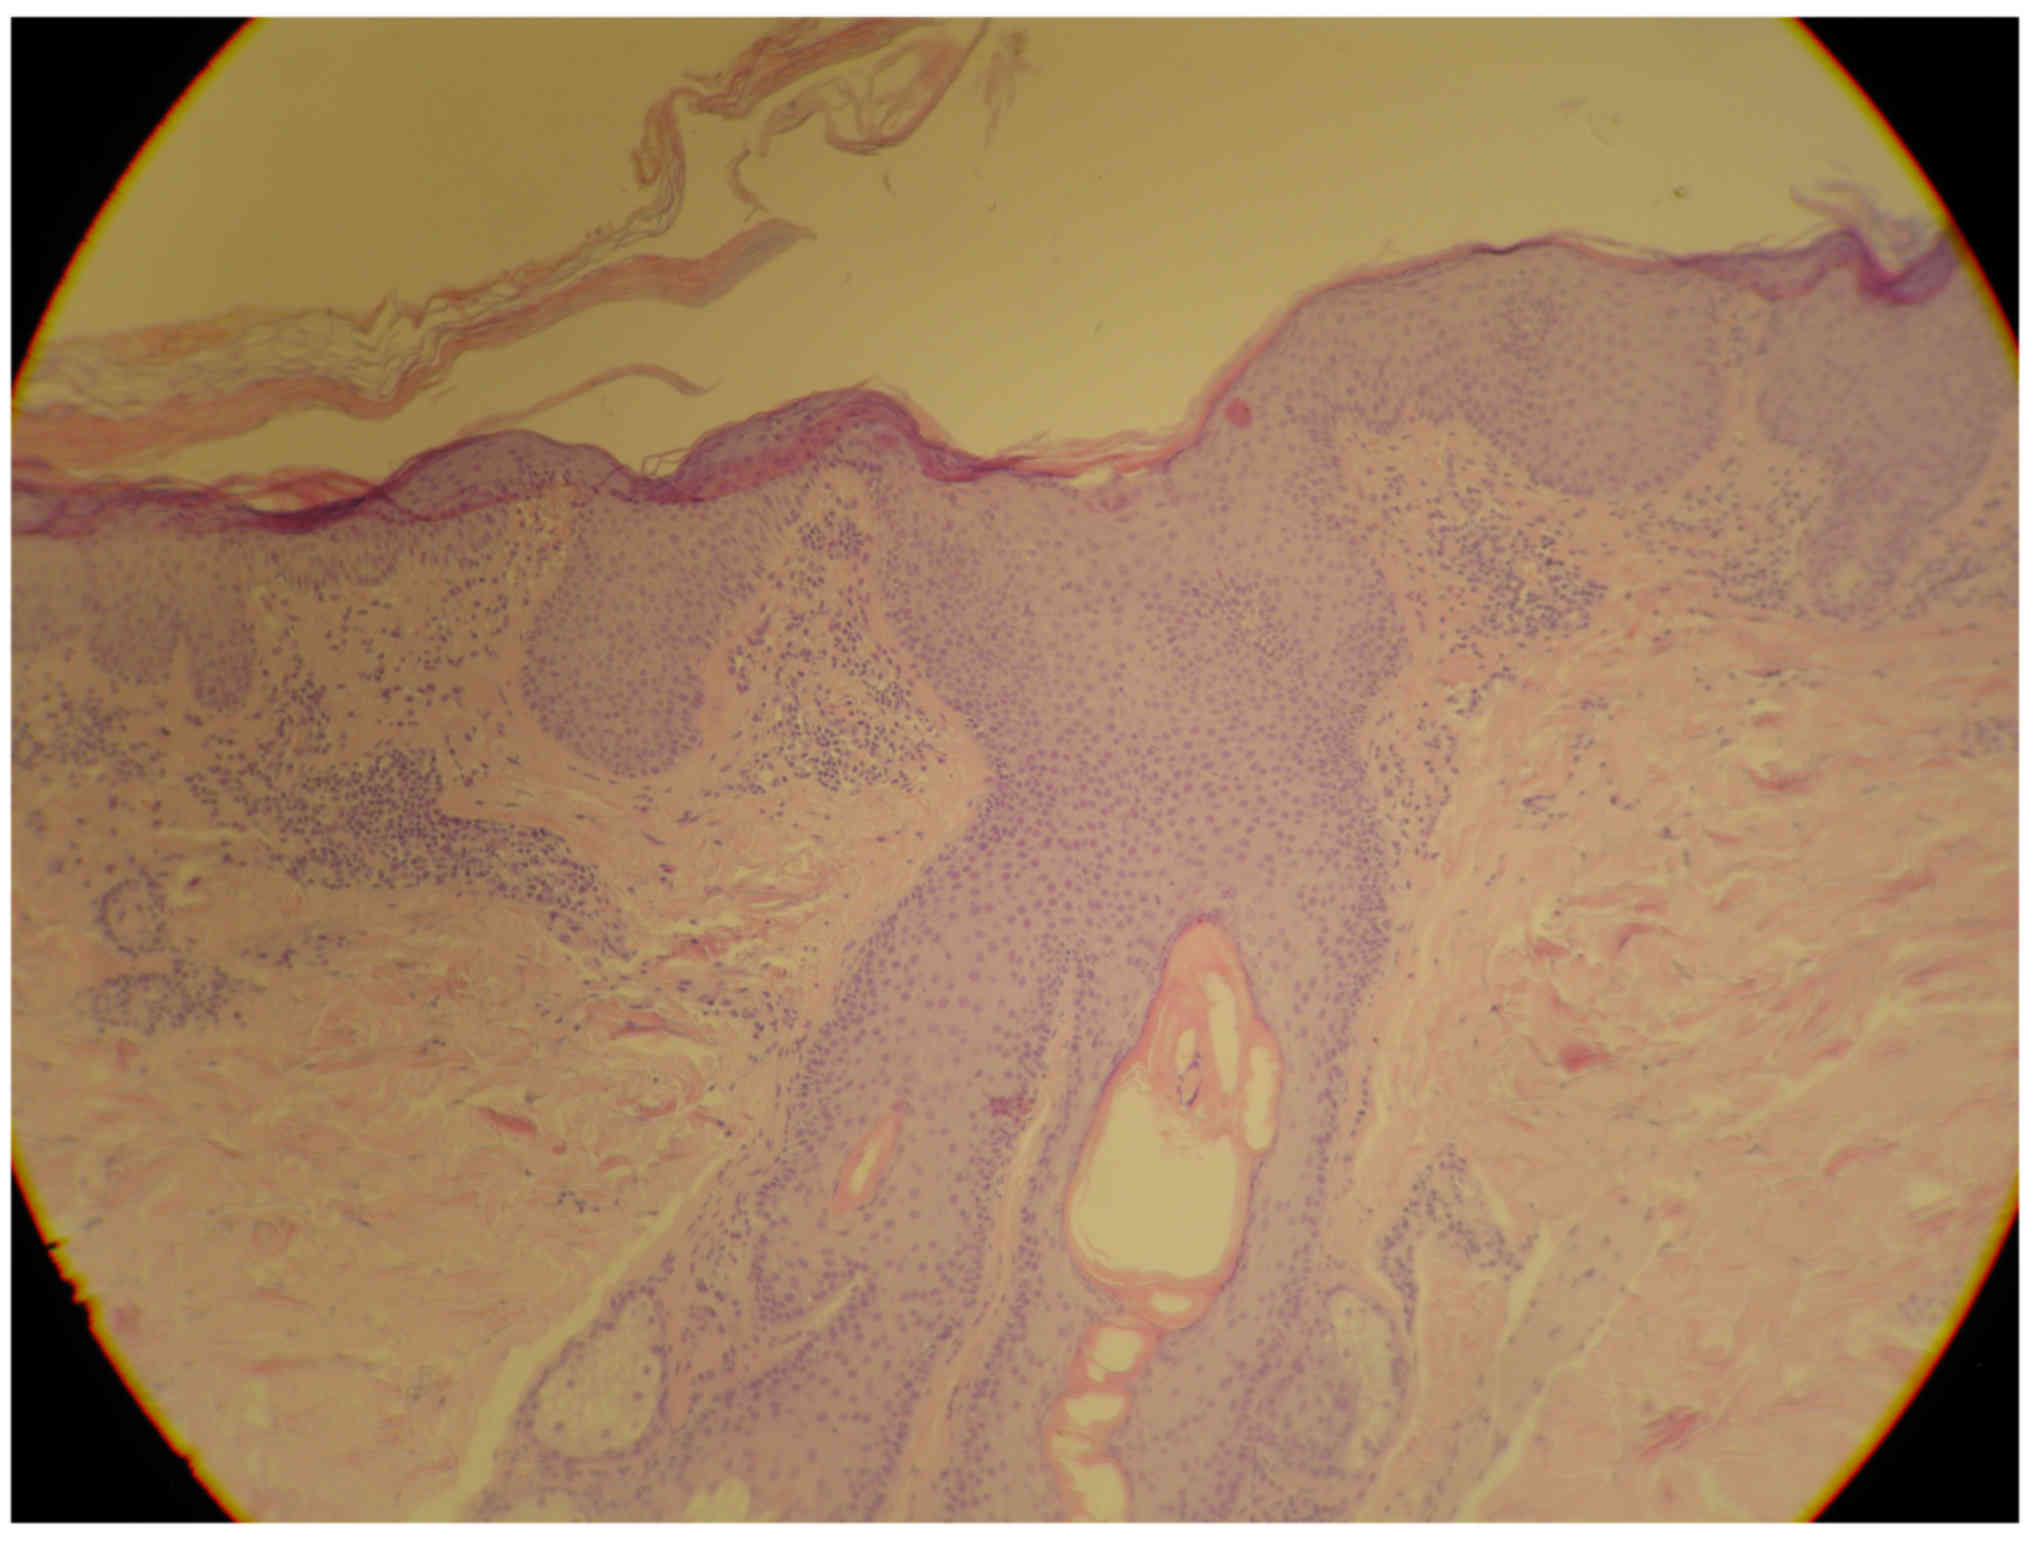

Figure 5.

Lamellar hyperkeratosis, focal hypergranulosis, typical follicular plugging with perifollicular parakeratosis, lymphocytic perivascular infiltration, hematoxylin and eosin staining; original magnification, ×10.